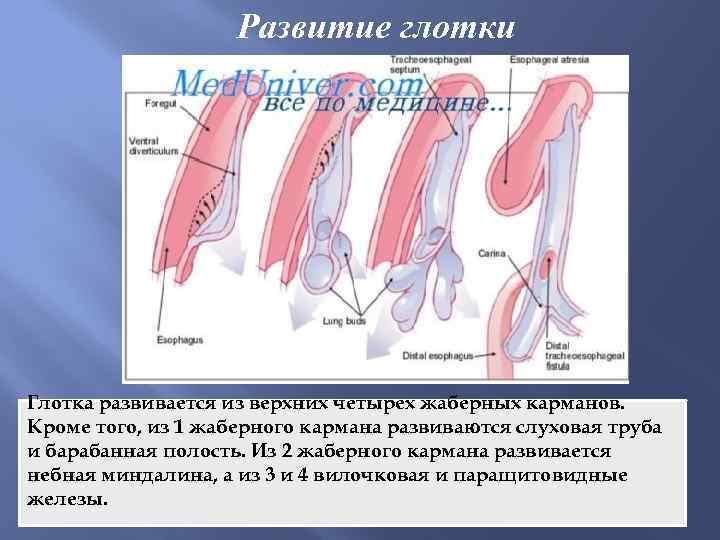

Развитие глотки Глотка развивается из верхних четырех жаберных карманов. Кроме того, из 1 жаберного кармана развиваются слуховая труба и барабанная полость. Из 2 жаберного кармана развивается небная миндалина, а из 3 и 4 вилочковая и паращитовидные железы.

Развитие глотки Глотка развивается из верхних четырех жаберных карманов. Кроме того, из 1 жаберного кармана развиваются слуховая труба и барабанная полость. Из 2 жаберного кармана развивается небная миндалина, а из 3 и 4 вилочковая и паращитовидные железы.